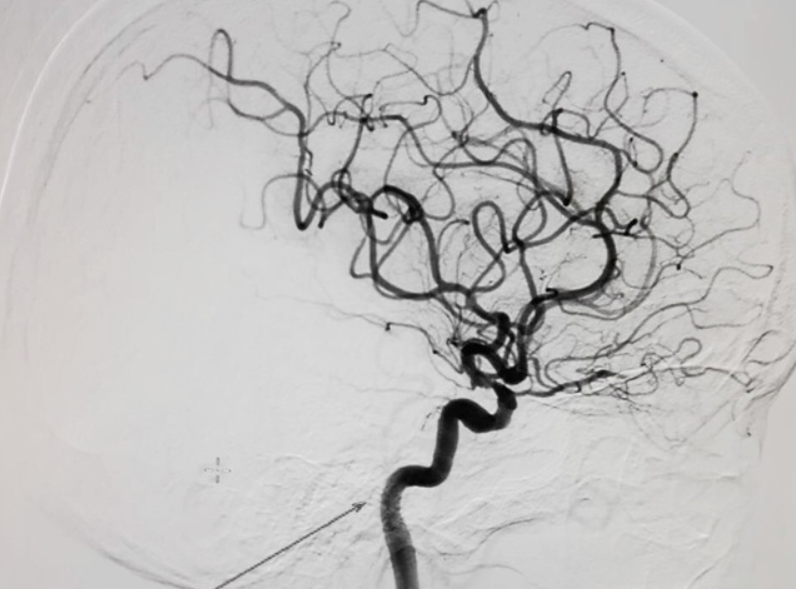

Chụp mạch máu số hóa xóa nền (DSA)

Đây là hệ thống chụp hình mạch máu thế hệ mới bằng tia X, với mục đích nghiên cứu máu trong cơ thể và để nhìn thấy rõ hơn các thương tổn cũng như những bệnh lý mạch máu trước khi có chỉ định can thiệp.

width= Hình ảnh chụp mạch máu số hóa xóa nền

Kỹ thuật này là sự kết hợp giữa việc chụp X-quang với xử lý số sử dụng thuật toán xóa nền trên 2 hình ảnh thu nhận được trước và sau tiêm chất cản quang vào mạch máu cần chụp. Sau đó, để làm rõ hệ thống mạch máu, máy tình sẽ tiến hành xòa mờ ảnh nền đi.

Chụp mạch máu số hóa xóa nền được sử dụng trong việc chẩn đoán và can thiệp điều trị:

• Đánh giá độ dị thường của động mạch chủ, động mạch cảnh, động mạch chi, động mạch thận và các động mạch ngoại biên

• Thông tim, nong hẹp van động mạch, đóng lỗ thông tim…

• Đặt lưới lọc tĩnh mạch chủ, lấy dị vật trong hệ tuần hoàn, đặt máy tạo nhịp, siêu âm trong lồng mạch và buồng tim…

Nhớ có chụp mạch máu bằng số hóa xóa nền, các bác sĩ phát hiện sớm bất thường của dòng máu. Từ đó, chẩn đoán và điều trị chính xác các bệnh lý nghiêm trọng trong lĩnh vực thần kinh và xác định chính xác vị trí tổn thương bên trong cơ thể, kể cả những vị trí sâu, khó phát hiện.